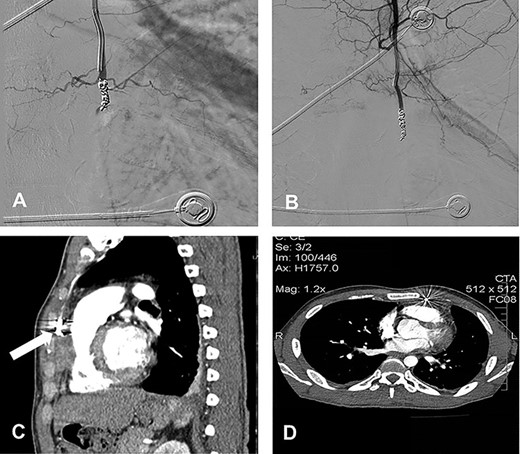

The embolization was performed after obtaining three consecutive negative blood cultures accompanied by a significant decrease of the laboratory infection parameters. The angiographic approach was done through the left brachial artery (Fig. 1D), and a microcatheter was placed into the aneurysm neck. Through coiling we aimed to occlude the IMA distally and proximally adjacent to the aneurysmatic sac, but attempts to cannulate the vessel distal to the aneurysm were unsuccessful. Therefore multiple (5x) coils were placed (VortX™ 35 (3×) and Complex Helical 18 (2×); Boston Scientific; Boston, MA, USA) into the aneurysmatic neck and sac (Fig. 2A).

(A) Coil embolization of the aneurysm; (B) postembolization completion angiogram; (C) follow-up contrast-enhanced CT scan at 3 weeks after the embolization with complete regression of the pseudoaneurysm without flow into it (white arrow); (D) follow-up contrast-enhanced CT scan at 6 months after the embolization.

The completion angiogram demonstrated no filling in the coiled pseudoaneurysmal sac (Fig. 2B), while at follow-up 1, 3 weeks and 6 months after the procedure, CT scans showed initially shrinkage and finally complete regression of the pseudoaneurysm with no flow into it (Fig. 2C and D; white arrow). Early post-interventional course was unremarkable, and the patient was discharged after completing an intravenous antibiotic treatment over 6 weeks.